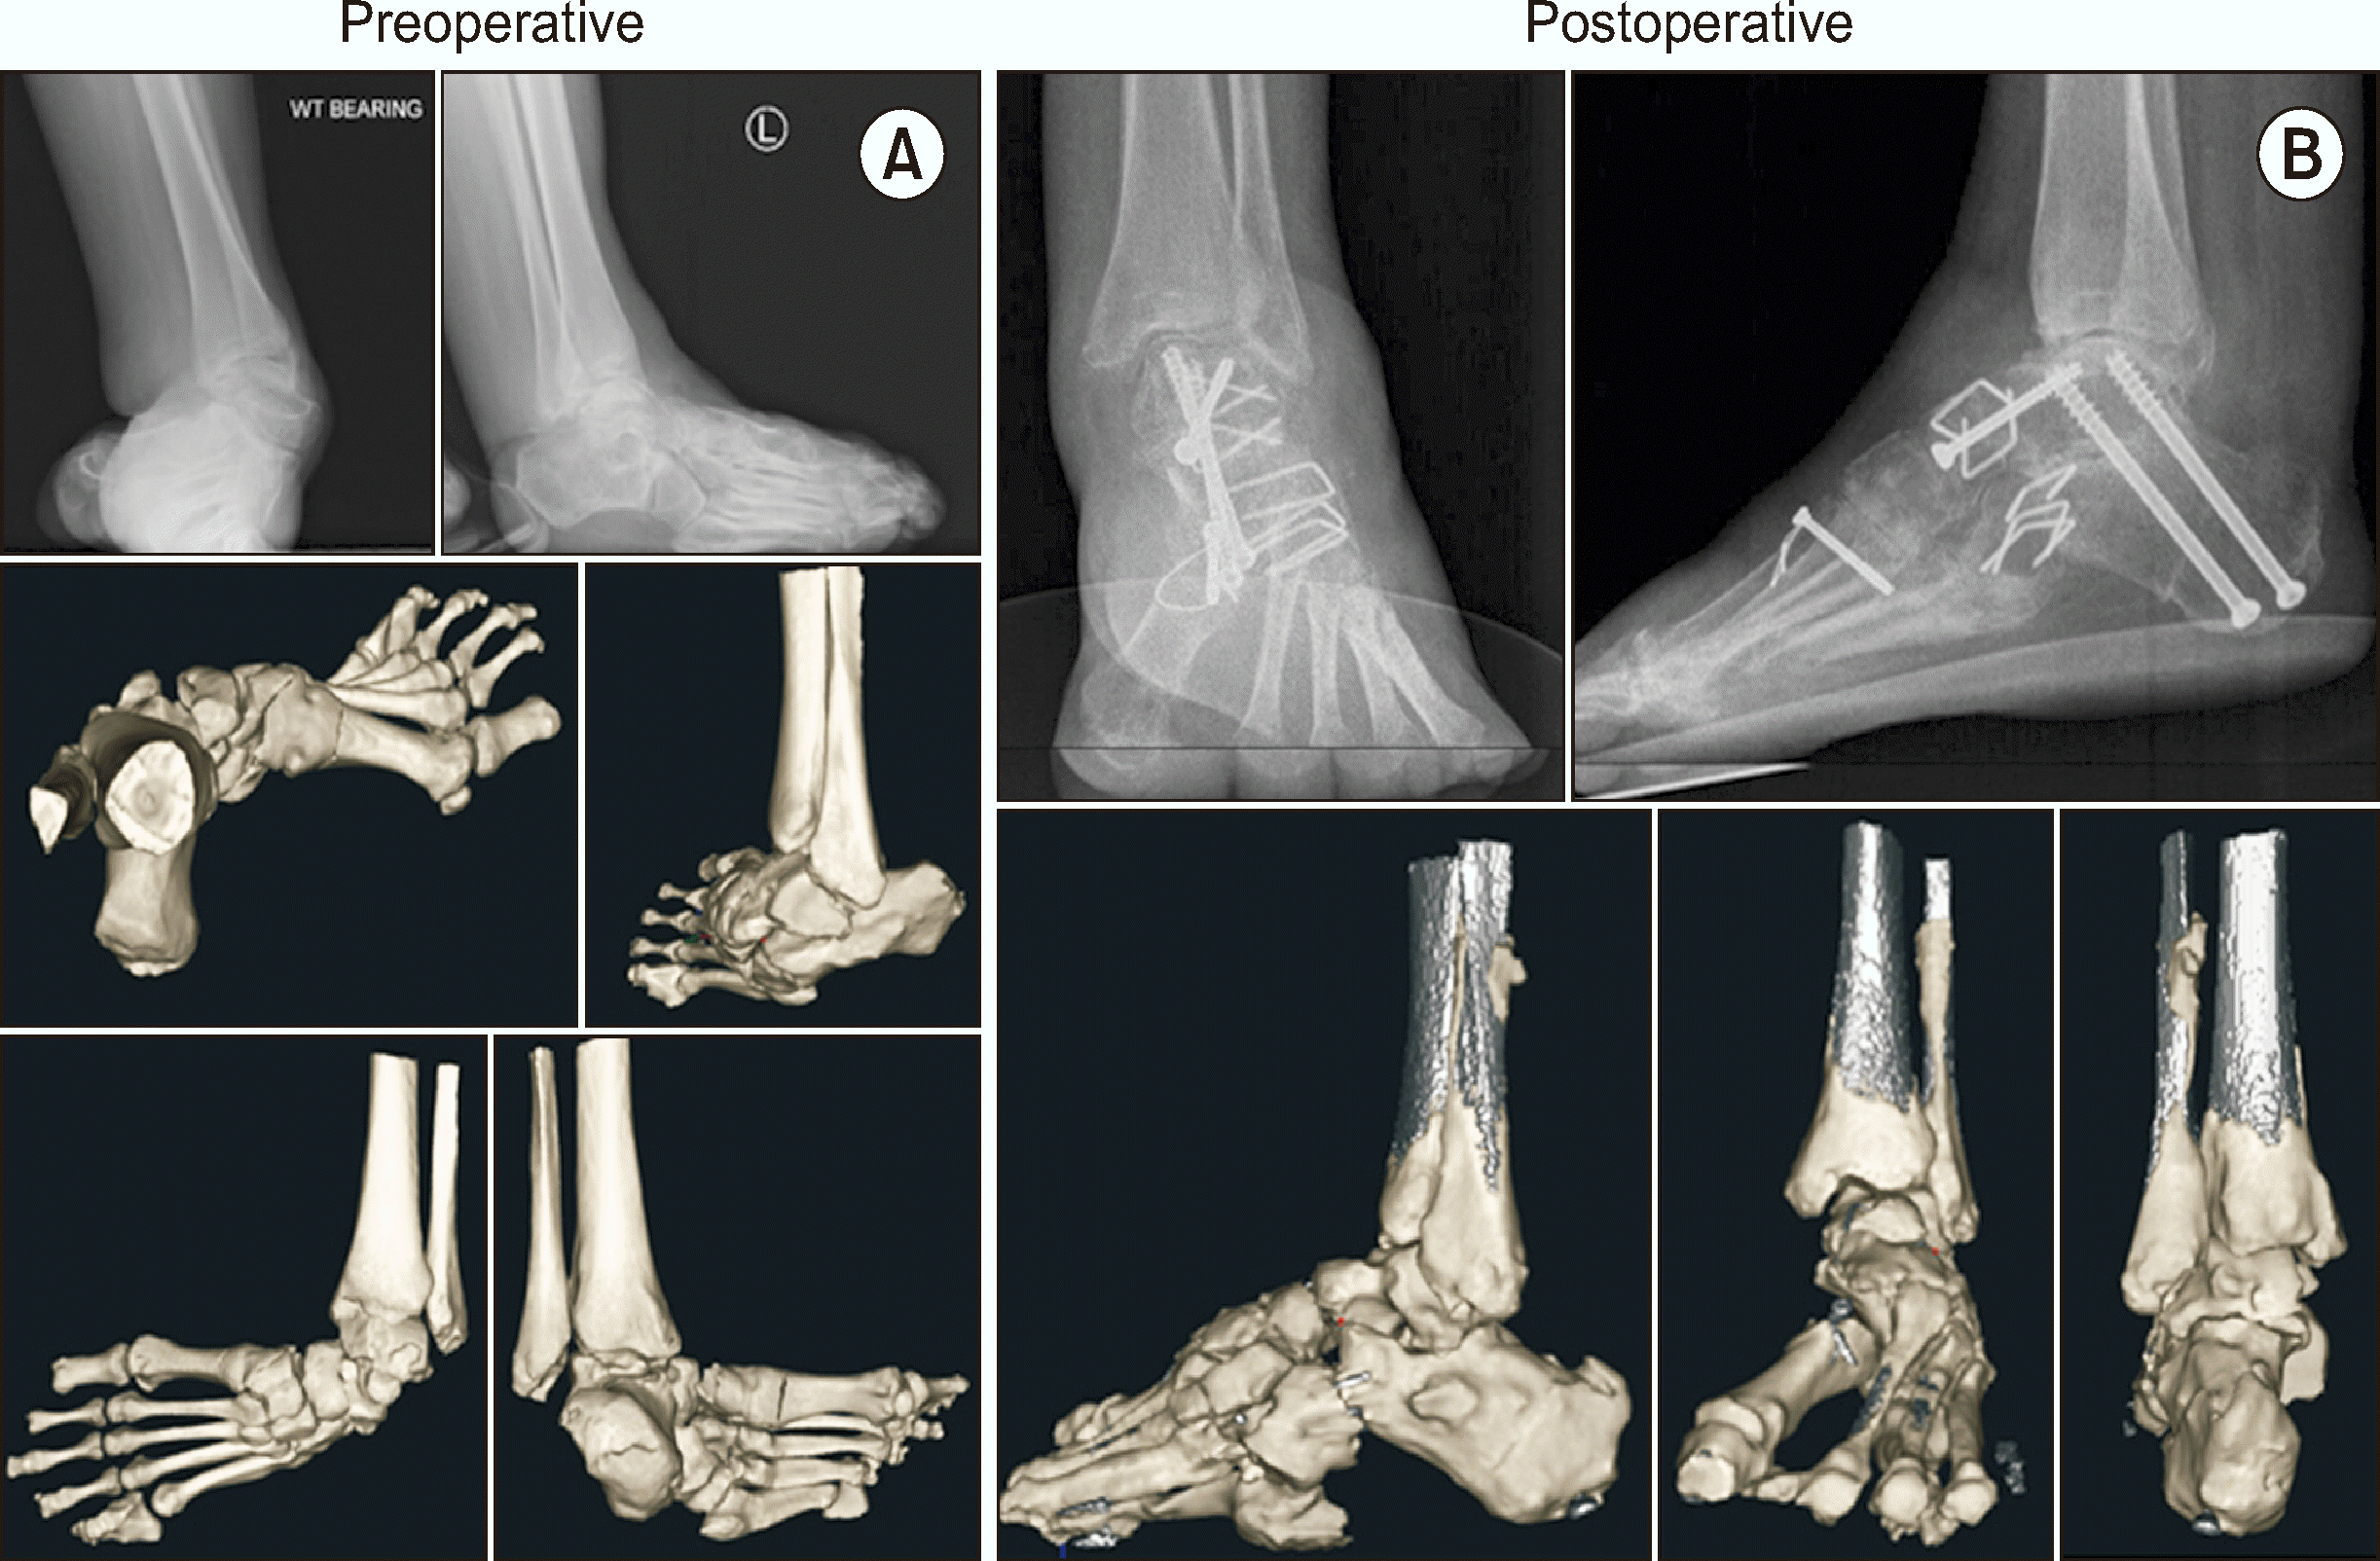

컴퓨터 단층촬영(computed tomography, CT)이나 자기공명영상(magnetic resonance imaging)은 술자가 필요한 경우에 선택적으로 시행한다. 특히 복잡한 변형을 보이는 CMT 족부 변형은 기존의 기립 단순 방사선 영상과 2차원 CT 영상으로 정확한 분석이 어려운 한계가 있어 관찰자간 신뢰도가 떨어지는 경우가 흔한데, 최근에는 체중부하 CT (weight-bearing CT, WBCT)와 3차원 자동화 분석 소프트웨어(3D automated analysis software)를 이용해서 CMT 족부 변형의 보다 정확한 분석이 가능한 것으로 보고되었다(Fig. 3).11,15,16) WBCT 영상은 특히 후족부 정렬 및 발목 관절 상합성(congruity) 이상을 파악하는 데 유용한데, 자동화 분석 소프트웨어를 이용하면 각 뼈들의 중심축 사이의 각도를 자동으로 계측하기 때문에 검사의 정확도와 신뢰도가 높은 것으로 보고되었다.1,11,16) Song 등11)은 CMT 족부 변형 환자에서 수술 전후 족부의 시상면, 축상면, 관상면의 다면적 정렬 평가 시 3차원 자동화 분석 소프트웨어를 이용한 WBCT 분석의 유용성을 보고한 바 있다. 그러나 이러한 영상의학적 도구들은 수술적 치료 방향에 도움을 줄 수 있으나 절대적인 골교정을 위한 지표가 될 수 없으며, 최종적인 골교정술의 결정은 모든 연부조직 유리술이 시행된 이후에 결정되어야 한다.1)

Song 등11)은 29명의 CMT 환자를 대상으로 진행한 관절 보존 술식의 효과를 수술 전후 족부의 WBCT 이미지를 자동화 분석 소프트웨어를 이용하여 분석하였고 연구 결과 관절 보존 술식이 CMT 족부의 시상면, 축상면, 관상면의 변형을 효과적으로 교정하였음을 보고하였다(Fig. 5). 또한 CMT 족부 변형의 교정에서 거주상 관절(talonavicular joint)의 연부 조직 유리술을 통한 관절의 정복이 가장 중요한 요소임을 보고하였다. 해당 연구에서 각 수술 사례에서 진행된 평균 술식의 개수는 7.8개(5∼10개)였고 각 술식은 환자 사례에 따라 선택적으로 시행되었다. 흔히 시행된 수술로는 수술 순서에 따라 경피적 아킬레스건 연장술(Achilles triple hemisection, 79.3%), 후경골건 유리술(82.8%), 거주상 관절 및 스프링 인대 유리술(89.7%), 경피적 장족지굴곡건 절단술(62.1%), 중족부 족저근막 유리술(93.1%), 장비골건 유리술(93.1%), 종골 절골술(82.8%), 장비골건의 단비골건 이전술(93.1%), 제 1중족골의 배측 폐쇄형 쐐기 절골술(86.2%) 및 후경골건 이전술(82.8%) 등이 있었다(Table 2).11) 그 외 시행된 술식으로는 신전건의 중족부 이전술(장무지신전건 및 장족지신전건을 각각 내측 및 외측 설상골로 이전), 장족지굴곡건 및 장무지굴곡건 이전술, 비복근 연장술 및 외측 발목 인대 봉합술 등이 포함되었다. 1차 수술 후 재수술이 필요하였던 사례는 후족부 정렬의 과교정으로 인해 재수술을 진행하였던 한 사례가 있었다.

Figure 5

Preoperative and postoperative radiographic results of the left foot of a 52-year-old female CMT patient who underwent joint sparing surgery. (A) Preoperative and (B) postoperative standing foot radiographs, weight-bearing 3D computed tomography images, and 3D model with segmental bone axes (red lines) generated by the software. CMT: Charcot–Marie–Tooth, WT: weight.